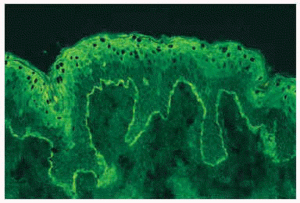

Los estudios de inmunofluorescencia directa muestran el criterio sine qua non del HG, que es el depósito de C3 con o sin IgG a nivel de la unión dermo-epidérmica (fig. 4). El uso de la técnica de piel hendida por inmersión en cloruro sódico 1 molar revela que los inmunorreactantes se depositan en el lado epidérmico con el mismo patrón que en el penfigoide ampolloso8. El microscopio electrónico los localiza preferentemente en los hemidesmosomas25. Por inmunofluorescencia indirecta se puede encontrar IgG circulante en el 25% de los casos, aunque este porcentaje aumenta si se emplean técnicas más refinadas26.

Fig. 4. Herpes gestationis. Estudio de inmunofluorescencia directa. Depósito de C3 en unión dermoepidémica.